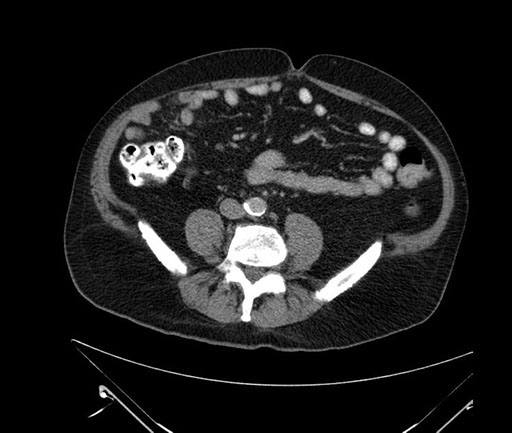

Axial - stented